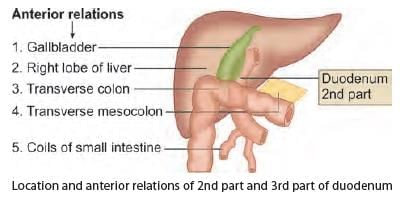

Anterior relations of third part of duodenum are all, except: (INI-CET May 2023)